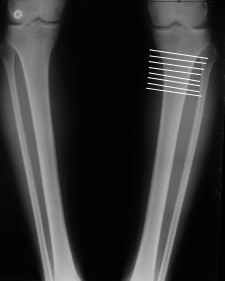

Судя по снимку у девушки имеется внутренняя установка надколенников...

Как у нее с торсионным статусом? Бедро? Голень? КТ? Торсиометры? А то, куда будут

смотреть надколенники после вашей коррекции - тоже существенный

косметический момент. Или не так?

AVM> Судя по снимку у девушки имеется внутренняя установка надколенников...

AVM> Как у нее с торсионным статусом? Бедро? Голень? КТ? Торсиометры?

Похоже, немного есть. Думаю пренебречь.

Вот, с учетом и без учета, и на разных уровнях...

Из приведнной схемы не совсеим понял что означают разноцветные линии.

И зачем латерализация периферического фрагмента. Я всегда делаю медиализацию. См схему. И для данного случая медиализация подходит как нельзя лучше.

Черные - это нынешняя механическая ось. Красные - это планируемая правильная ось.

Мне представляется оптимальным на уровне 3-4 линии (т.е. как раз посредине отмеченной зоны). Если рассчимтываешь делать медиализацию, то параллельно суставной поверхности, иначе просто не сдвинешь без джистракции - отломки зацепятся. Если без медиализации - то вообще не имеет значения.

4. Если внимательно посмотришь на рентгенограммы, то в зоне перелома малоберцовой кости она втягиваетсмя внутрь, таким образом немного уменьшая объем тканей по внутреннему контуру. Причем чем выше - тем эффектнее. Не надо только совсем высоко лезть - там перонеус. Многих пайциенток это тоже смущает. Так что решаем проблему комплексно. На это, кстати, особо упирает Казбек Кудзаев.